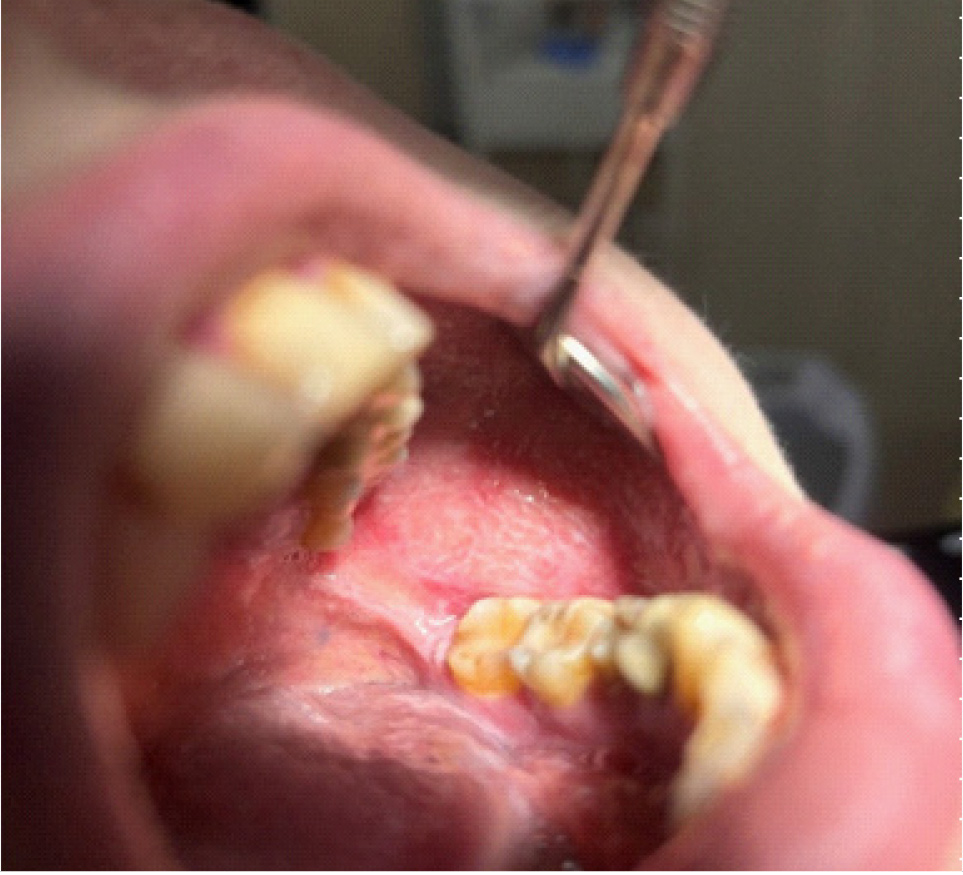

Пациент Р., 82 года, обратился в кабинет хирургической стоматологии с жалобами на острый край нижней челюсти. В ходе осмотра полости рта обнаружено нарушение целостности слизистой оболочки с субтотальным остеонекрозом альвеолярной части нижней челюсти во фронтальном отделе.

В полости рта: нарушение целостности слизистой оболочки полости рта, субтотальный остеонекроз альвеолярной части нижней челюсти слева. Вид костной тканей серо-коричневого цвета, пальпация безболезненная. На ортопантомограмме отмечается ограниченный участок деструкции костной ткани нижней челюсти с поражением тела нижней челюсти. Одонтогенной причины заболевания нет (рис. 1).

Рис. 1. Клинические проявления бисфосфонатного остеонекроза нижней челюсти во фронтальном отделе